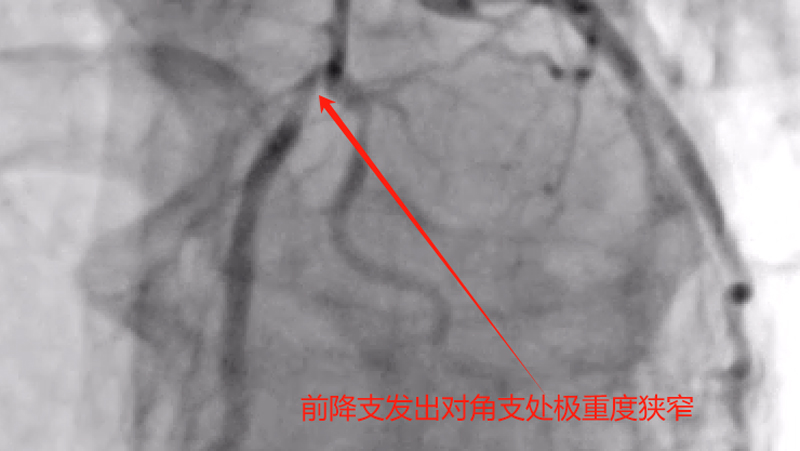

据了解,吴某,男性,58岁,因胸痛就诊,确诊为急性非ST段抬高型心肌梗塞,10多天前有过消化道出血情况,既往有心肌梗塞、痛风、慢性肾功能不全等病史,1年前胃镜提示有胃溃疡病史,口服有多种药物,考虑患者病情危重及复杂,心血管内科介入团队经过讨论后先行冠脉造影后再决定下一步诊疗策略,造影可见:前降支中段发出对角支后极重度狭窄,可见侧支循环右冠中远端,回旋支发出钝缘支后闭塞,可见钝缘支侧支循环回旋支远端;右冠中段闭塞。

经过医护人员精心照顾及治疗,患者各方面情况相对稳定,11月5日心血管内科介入团队再次为患者行冠脉介入治疗。并顺利开通右冠闭塞血管并植入支架恢复正常血流,同期解决前降支极重度狭窄病变并植入支架解除危机。手术总用时1小时40分钟,造影剂用量120ml。